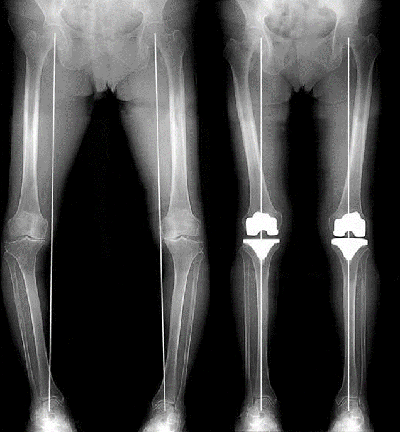

変形性膝関節症の術前

高位脛骨骨切り術

骨切り術の術後

人工膝関節全置換術(左:手術前、右:手術後)

人工関節置換術には、ひざの関節すべてを人工関節に取り換える全置換術と、変形した部分のみを取り換える単顆片側置換術があります。全置換術はデザインや材質、手術方法が確立されており、変形性膝関節症に対して最も多く行われている手術です。

当院では人工関節の適切な設置が手術後の成績に最も影響を与えることを考慮し、術前に3D-CTを撮影し、コンピューター支援により、患者さんの膝に最も適した人工関節サイズと設置位置を想定して手術を行っています。